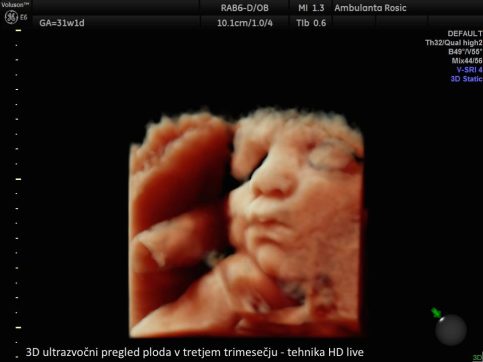

V sklopu 3D/4D ultrazvoka ploda je preiskavo mogoče opraviti tudi v tehniki HD live, pri kateri lahko s pomočjo posebnih tehnik osvetljevanja, senčenja ter virtualnega izvora svetlobe plod prikažemo neverjetno realistično.

3D/4D ultrazvok v nosečnosti izvajamo z vaginalnim (nožničnim) ali abdominalnim (trebušnim) tipalom. Vaginalno tipalo uporabljamo pri ultrazvočni preiskavi v prvem trimesečju, abdominalno tipalo pa v drugem in tretjem trimesečju nosečnosti. S tem imate pri nas nosečnice možnost opraviti 3D/4D ultrazvok ploda že od prvega pregleda v nosečnosti dalje.